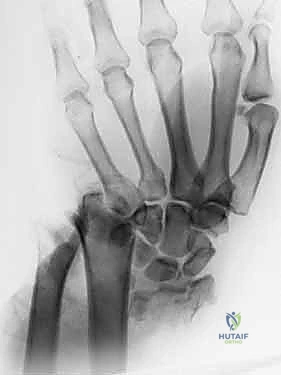

- الأشعة السينية (X-rays):

هي الخطوة الأولى لتقييم الكسر. يتم أخذ صور من زوايا متعددة (أمامية خلفية، جانبية، ومائلة) لتحديد موقع الكسر الأساسي ودرجة الانزياح والتقصير في عظم الكعبرة.